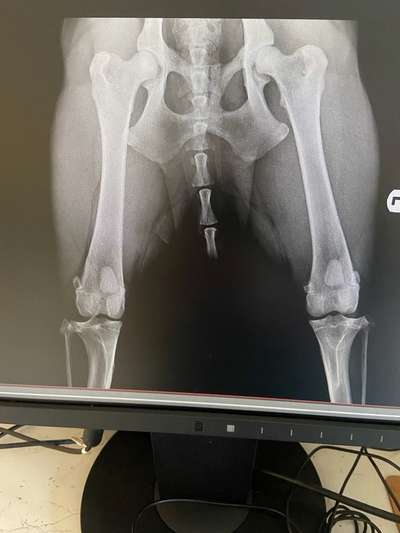

Guten Morgen 🤗 ich wollte euch mal ein paar Neuigkeiten mitteilen und erst einmal:Keine Sorge,dass ist nicht die Hüfte von Puma,zum Glück,ihre ist in Ordnung. Das ist die Hüfte von einer von Pumas jüngeren Schwestern,die ist 10 Monate alt und hat dieses Problem schon von Geburt an.Ist natürlich deswegen auch etwas anders gelaufen,die jetzigen Besitzer haben die mit 6 Monaten bekommen,aber die Züchter haben nichts gesagt.Ein Anwalt ist eingeschaltet und hoffentlich dürfen die nie wieder züchten.Ich habe da einiges Neues erfahren,was ich vorher noch nicht gewusst habe und meine Meinung ist sogar schon im unteren Teil des negativen Bereiches,wobei ich vorher dachte,die könnte nicht weiter runtergehen. So ein Fehler passiert mir kein zweites Mal und bin einfach nur froh,dass ich auch nur die normalen Hundeprobleme mit Puma in dem Alter habe und sie bisher keine gesundheitlichen Probleme aufweist.

Das war die Röntgenaufnahme von Puma